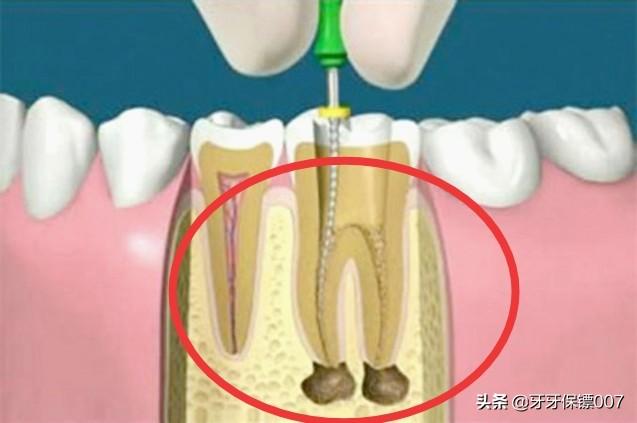

Par exemple, le plus courant est le traitement du canal radiculaire, en cas de pulpite ou de nécrose pulpaire, qui consiste d'abord à retirer la pulpe malade, ce qui permet de résoudre le problème des maux de dents et, ensuite, de faciliter la restauration dentaire en portant des couronnes en porcelaine.

J'ai décidé de faire un traitement de canal seulement après avoir confirmé avec le médecin encore et encore. Au début, j'ai aussi baidu quelques informations, beaucoup de gens disent ne pas avoir un traitement de canal, un bon médecin ne proposera pas d'aller au traitement de canal ? Parce qu'après tout, la dent après le canal radiculaire ne peut pas absorber les nutriments à travers l'alvéole, de sorte que la dent ne fera que s'aggraver de plus en plus, et finalement jusqu'à la fin de l'irréparable. Le traitement de canal implique également le port d'une couronne, sans parler du prix de la couronne, de son élégance, etc. ...... Je n'aime donc pas beaucoup le médecin qui m'a proposé de me faire un traitement de canal.

Si la carie est particulièrement grave et a endommagé le nerf de la dent, un traitement de canal peut être effectué en premier lieu pour éliminer la carie et l'inflammation. Si la partie restante de la dent est trop petite, un inlay peut être réalisé, ou une couronne peut être fabriquée pour la protéger et essayer de ne pas extraire la dent.